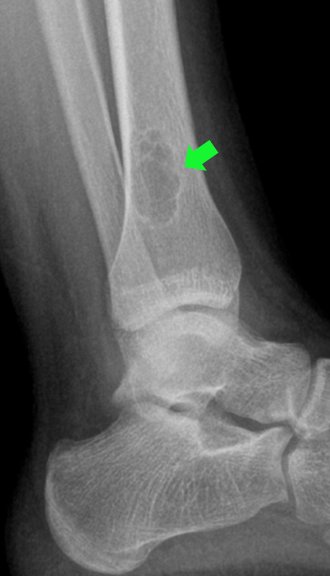

Kemiğin duvarından gelişebilen iyi huylu bir tümör de “fibröz kortikal defekt”tir. Nadiren ağrı yapar yada kemiğin duvarını zayıflatabilir. Çoğu zaman başka bir nedenle çekilen röntgende tesadüfen saptanır (resim-15). Büyük oranda ameliyat gerektirmez ve kendiliğinden iyileşme gösterir. Ancak fazlaca büyüyüp kemiğin büyük kısmını etkilemişse ameliyatla temizlenmesi gerekir. Aksi halde “patolojik kırık” dediğimiz kemiğin aşırı zayıflamasına bağlı kırık durumu gelişebilecektir (resim-16). “Non-ossifiye fibrom” içinde benzer şeyler söylemek mümkündür (resim-17).

Patolojik kırıklar her kemik tümörü zemininde gelişebilir. Kemik duvarlarının tümör nedeniyle aşırı zayıflaması nedeniyle ortaya çıkar. Kemik sarkomlarında meydana gelirse tedavi çok zorlaşır. Çünkü bu durumda kötü huylu olan tümör hücreleri her yöne yayılır ve olay çok daha kompleks bir hale gelir. İyi huylu kemik tümörlerinde de aynı durum gözlenebilir. Bu durumda da tedavi daha kompleks hale gelecektir.